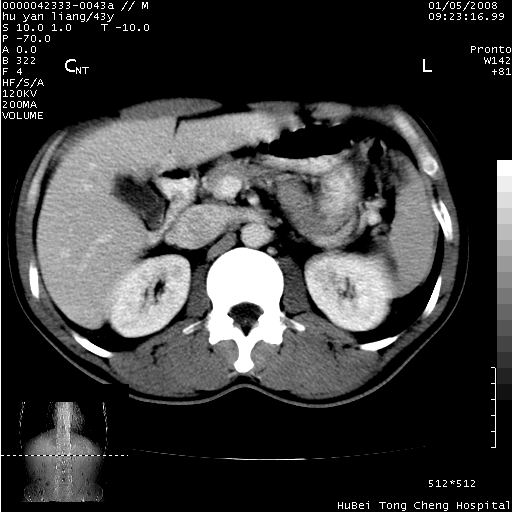

患者 男,43岁。右上腹不适1年余。既往有“肝右叶肝脓肿”病史,经保守治疗后痊愈。

b超提示:1)肝右叶肝内胆管结石。2)肝右叶占位性病变待排。

上中腹部ct轴位平扫+增强扫描(层厚10mm,螺距1.0,重建间隔10mm),图像如下:

肝右上叶偏后方较大团片状钙化灶,支持:肝脓肿后遗改变!

肝右叶后段团块状钙化灶,结合病史考虑肝脓肿痊愈后表现。